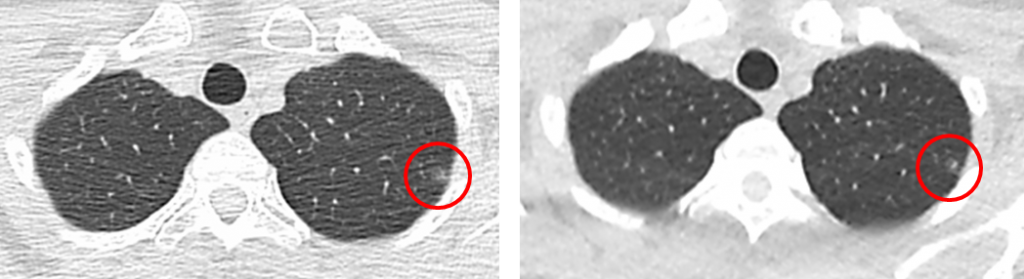

54歲不抽菸女性,母親有肺癌。該女士2012年1月健檢時,透過低劑量電腦斷層檢查,發現左上肺葉有毛玻璃小結節5.9mm(左圖)。

2018年1月追蹤,小結節為6.1mm;同年6月再檢時,影像圖如右(因距上次檢查時間近,因此未測量結節大小)。患者於2018年8月在某醫院接受手術,病理結果為「肺腺癌」原位癌。